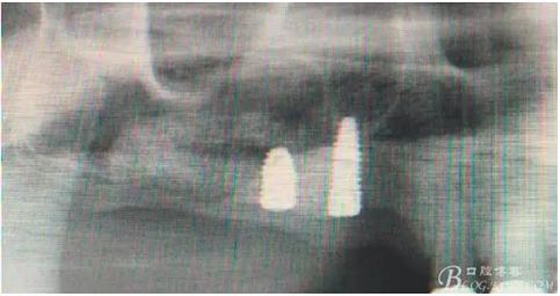

術(shù)后40天X光片。